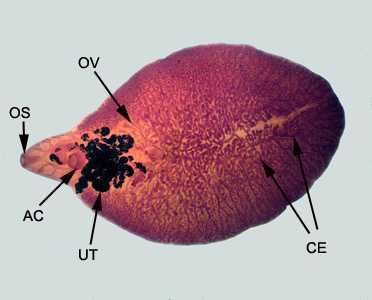

Figure D

This was a case of fascioliasis, caused by the liver fluke, Fasciola hepatica, a large trematode that resides in the bile ducts of the definitive host. Diagnostic features, best seen in the carmine-stained specimen in Figure D, included:

- the presence of oral (OS) and ventral (acetabulum, AC) suckers.

- branching ovaries (OV) and uterus (UT), the latter of which appears dark in carmine-stained specimens.

- extensive branching of the intestinal cecum (CE).

Figure D